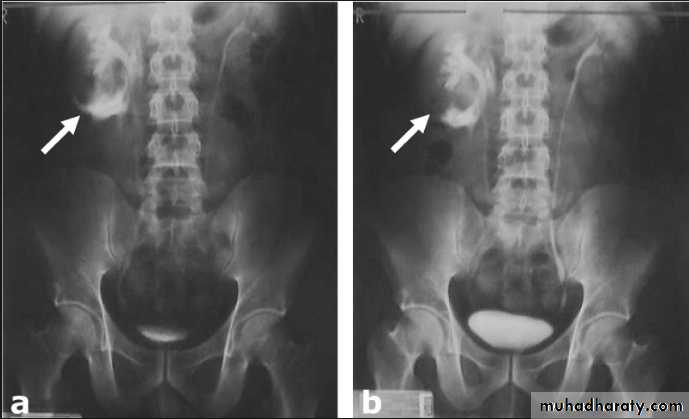

l.V.U. findings:

-Plain film may be useful in demonstrating calculi. -After contrast injection: Acutely obstructed kidney shows a dense nephrogram (dense opacification of the renal parenchyma).

excretion of contrast (opacification of the collecting system which may take many hours) ,

then the level and degree of obstruction can be determined as dilated pelvi-caliceal system and ureter are followed down to the point of obstruction (point of hold up).